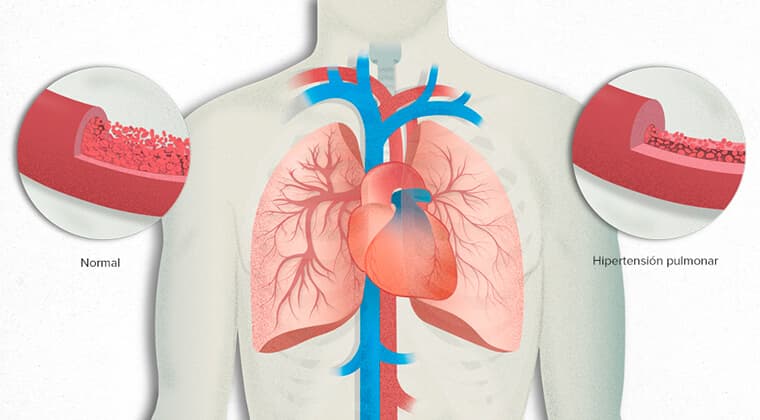

Hipertensión pulmonar

Aumento anormal de presión en las arterias de los pulmones, causando falla cardíaca progresiva.